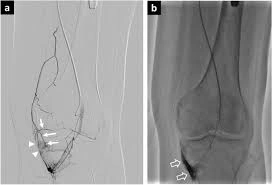

GAE for Osteoarthritis Knee

What is GAE?

Genicular Artery Embolization (GAE) is a minimally invasive treatment used for knee osteoarthritis pain.In this procedure, tiny particles are injected into the genicular arteries (small arteries around the knee) to reduce inflammation and pain.